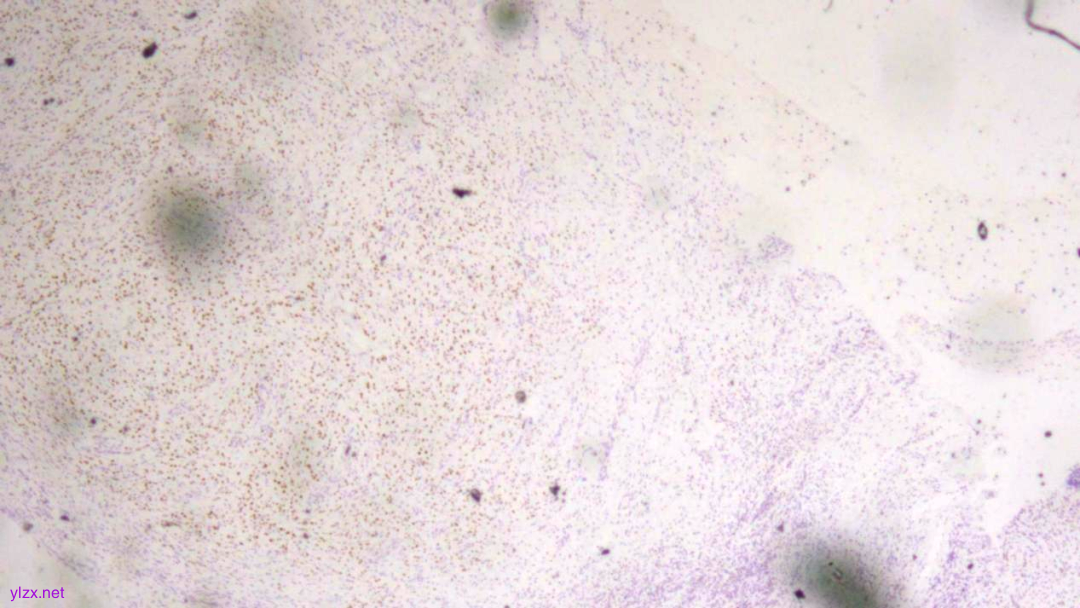

Ki-67(散在+)

ki-67(个别细胞+)